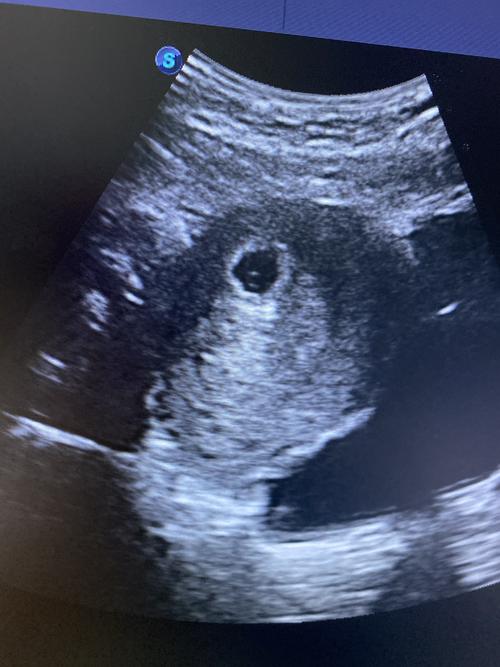

拍的孕囊,现在有两个闺女,想要个皮夹克,这个孕囊能看出来男孩女孩吗?

怀孕期间是不能根据孕囊大小来判断男孩和女孩的,胎儿的性别是在精子

怀孕早期,有"看孕囊形状判断胎儿性别"的说法:长条形的就是男孩,椭圆